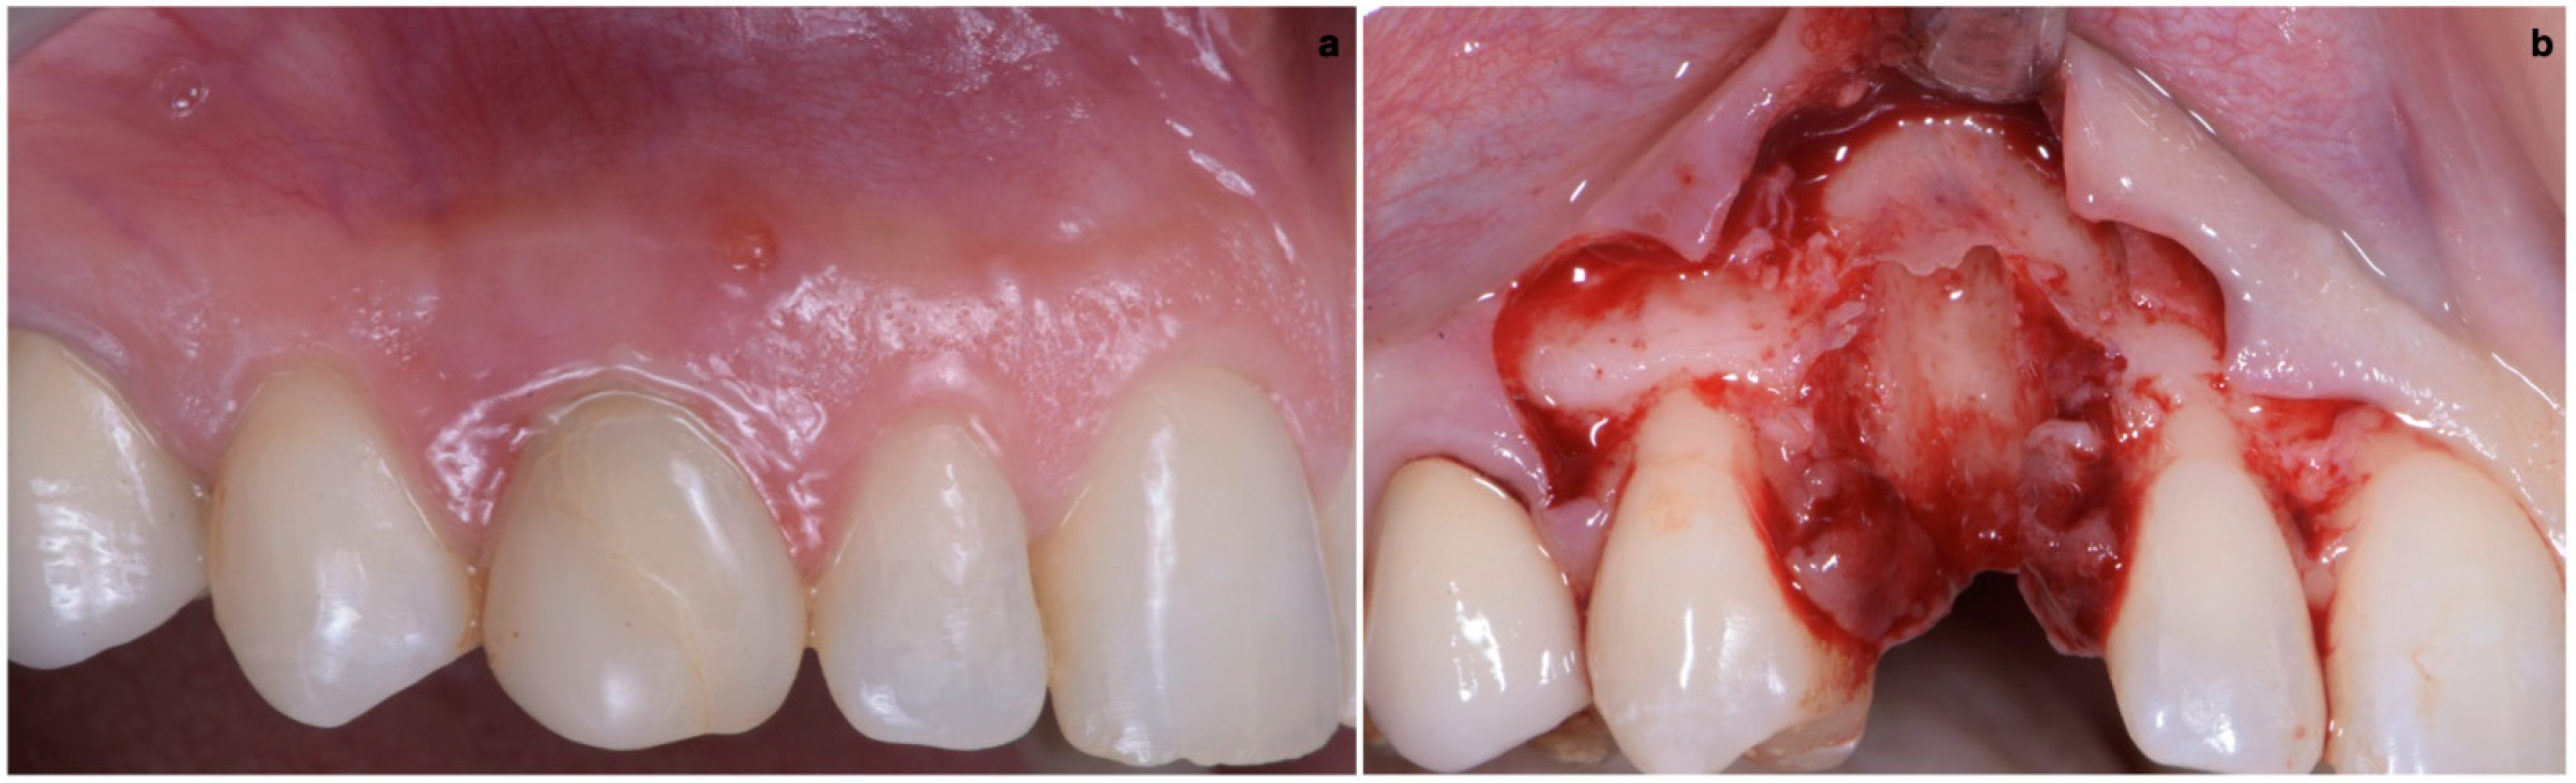

2.3. Provisional Restoration

As shown in Figure 13, the maturation of soft tissue at 1 month (a), 3 months (b) and 6 months (c) after surgery was evident. The peri-implant soft tissues were conditioned with the provisional crown until the shape and position for the mucosal scallop to resemble the gingival margin of the adjacent corresponding tooth and the progressive growth of peri-implant papillae were obtained [19]. In this phase, the patient was called every 2 weeks for us to check the provisional restoration. At the end of the conditioning phase, it was possible to place the definitive, screw-retained restoration (Figure 14a–c).

2.4. Final Result

One year after final restoration placement, the clinical outcome remained stable and fully satisfied the patient’s esthetic demands (Figure 15a–c). The soft tissues were morphologically and dimensionally stable without any signs of inflammation, and the marginal bone loss evaluated with periodical X-ray scans was minimal (Figure 16).

Figure 13. Maturation of soft tissue at 1 month (a), 3 months (b) and 6 months (c) after surgery.

Figure 15. (ac) One year after final restoration placement, the clinical outcome remained stable and fully satisfied the patient’s esthetic demands.